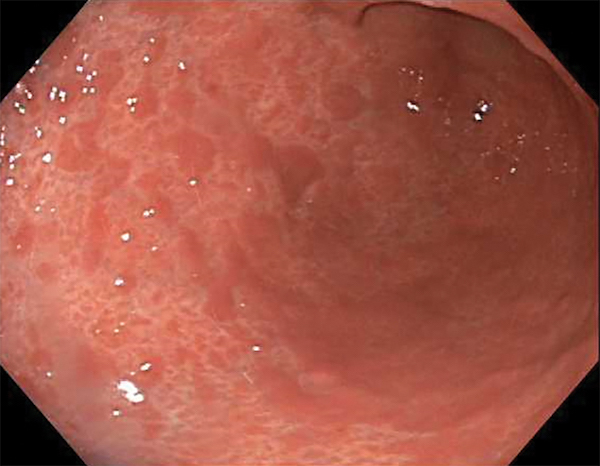

On physical exam, her vital signs are normal. There is mild conjunctival pallor, and mild epigastric tenderness on palpation, but no other pertinent findings. Complete blood count shows a hemoglobin of 10 g/dL with a mean corpuscular volume of 77 fL and a peripheral eosinophil count of 1.1 cells x 109/L. Upper endoscopy is performed and a view of the stomach is shown in the figure. Biopsies of the esophagus and duodenum are normal, but the stomach has sheets of infiltrating eosinophils with 100 eosinophils per high-power field diffusely. Which of the following tests should be performed before eosinophilic gastritis can be diagnosed?

This endoscopy shows prominent erythema and nodularity in the gastric body and antrum, and is suggestive of eosinophilic gastritis (EG), though the findings are nonspecific. The biopsies are also highly suggestive of EG, as is the peripheral eosinophilia. However, prior to a diagnosis of EG, causes of secondary eosinophilia must be considered and excluded as necessary. Given this patient’s history, there is a concern for an occult parasitic infection (though normal duodenal biopsies make this less likely) so stool for oval and parasites, and potential serology for other parasitic infections should be assessed. The endoscopic findings likely explain the patient’s mild anemia, and laboratory test results are not consistent with a hemoglobinopathy so hemoglobin electrophoresis is not needed. While rheumatologic and connective tissue disorders can be rare causes of eosinophilia, there is nothing to suggest these diagnoses on history and physical, and since a diagnosis of vasculitis or temporal arteritis is not being entertained, temporal artery biopsy is not indicated. While celiac disease can present with anemia and weight loss, the normal biopsies exclude this condition so further serology is not needed.